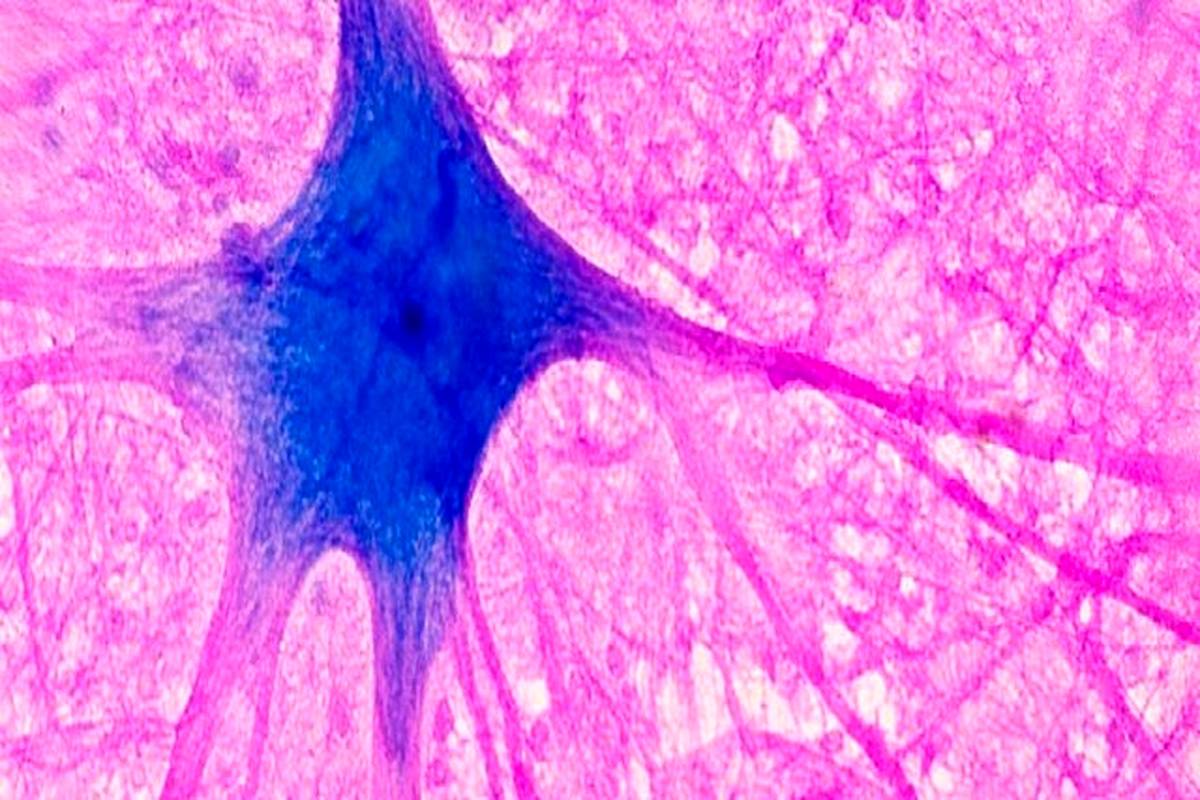

«متیلن بلو» میتواند از مانع حفاظتی اطراف مغز(سد خونی مغز) عبور کند و وارد آن شود. دانشمندان همچنین دریافتهاند که این ماده میتواند از «میتوکندریها»(mitochondria) که بهعنوان موتورهای سلولی توصیف میشوند، محافظت و پشتیبانی کند. این ماده ممکن است به «میتوکندریها» کمک کند تا انرژی را برای استفاده سلولها تولید کنند. به همین دلایل، دانشمندان در حال مطالعه تأثیر «متیلن بلو» بر مغز هستند.

بیشتر آنچه درباره تأثیرات این ماده بر مغز تاکنون شناخته شده است، از مطالعات بر روی موشها و سلولهای رشد یافته در ظروف آزمایشگاهی ناشی میشود. مطالعات بر روی جوندگان همچنین نشان داده است که این ماده میتواند از مغز در برابر آسیب ناشی از ضربه مغزی محافظت کند. با این حال، هیچ مطالعهای تاکنون بررسی نکرده است که آیا این ماده میتواند مغز انسانها را از آسیب مغزی یا سکته مغزی محافظت کند یا خیر.